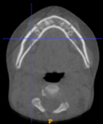

Three points determined the Acta plane: O, F right (FR), and F left (FL) (Table 2). Point O is the midpoint between the most craniodorsal point of the dorsum Sella and the most posterior dorsal point of the Basion in the midsagittal plane (Figure 1). Both points F are a result of the intersection between two lines: the line that connects the most inferior points of the lower orbital margins, right and left, and a line perpendicular to this line that runs through the most external points of the orbital margins, right and left (Figure 2). The new transverse reference plane, the Acta plane (Figure 2), is created by connecting the O-point (Figure 1) with FR and FL (Figure 2).

Figure 1.

Point O (green dot) is the midpoint between the dorsum Sella (Se) (red dot) and the Basion point (Ba) (yellow dot).